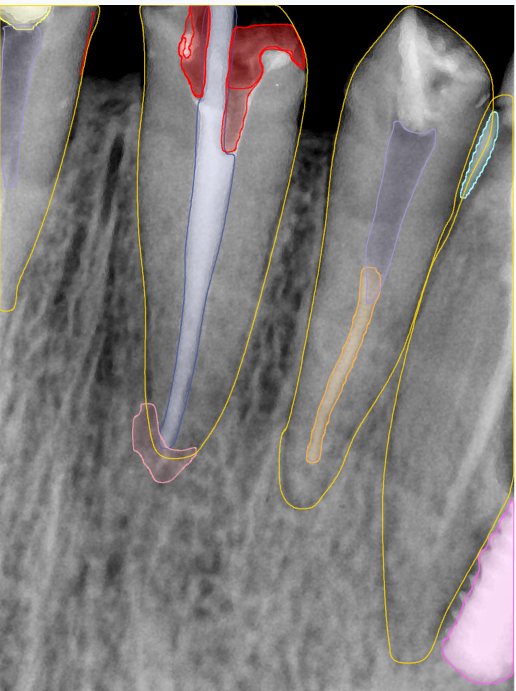

CR/DR 牙齿分割阶段记录

当前进展

- 完成了 CR/DR 牙齿相关分割训练

- 当前结果已经达到阶段预期,但仍有细节问题需要继续处理

相关测试

遇到的问题

- 训练过程中出现过 mask 下移问题

- 部分结果会出现 box 填充异常

- mask 边缘仍然有比较明显的锯齿感

第二版算法问题测试